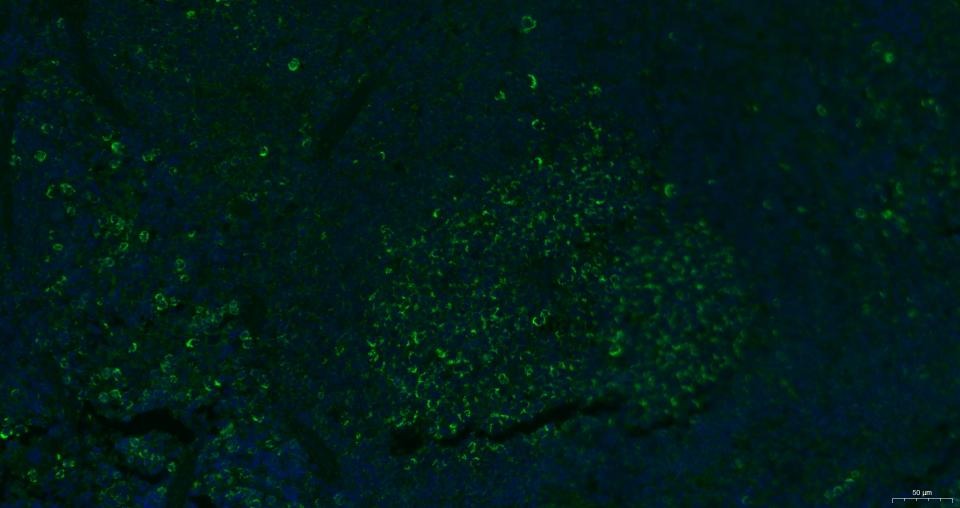

2. Paraformaldehyde-fixed, paraffin embedded Rat spleen; Antigen retrieval by boiling in sodium citrate buffer (pH6.0) for 15 min; Antibody incubation with CXCR4 Polyclonal Antibody, Unconjugated (TMAB-00509) at 1:200 overnight at 4°C. Followed by conjugated Goat Anti-Rabbit IgG antibody (green), DAPI (blue) was used to stain the cell nucleus.